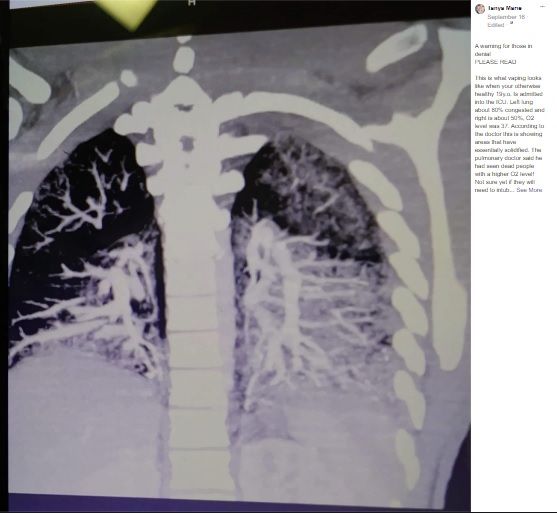

そんななか、電子タバコ歴2年の男性(19歳)の両親が、息子の肺のレントゲン写真をSNSで公開し注意を喚起した。

両親は医師から「アンソニーさんの肺は70歳のヘビースモーカーと一緒で、完全に回復するかは分からない」と告げられ、レントゲンの写真を見せられて言葉を失った。

アンソニーさんの肺は左肺の80%、右肺の50%がうっ血しており、呼吸がうまくできているかどうかの指標となる酸素飽和度は37%しかなかった。

メイヨー・クリニックによると、酸素レベルが90%以下になると呼吸不全となり危険な状態であるという。